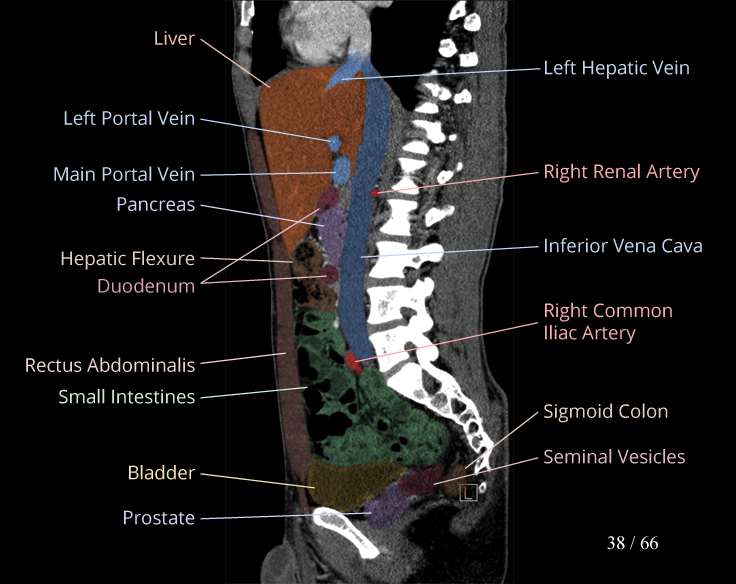

Body

Covers abdominal CT anatomy.